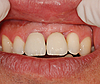

Cette dent présente une récession gingivale qui a favorisé l'apparition d'une carie.

La réalisation d'une greffe gingivale a permis de protéger la racine et de préserver l'avenir de la dent.